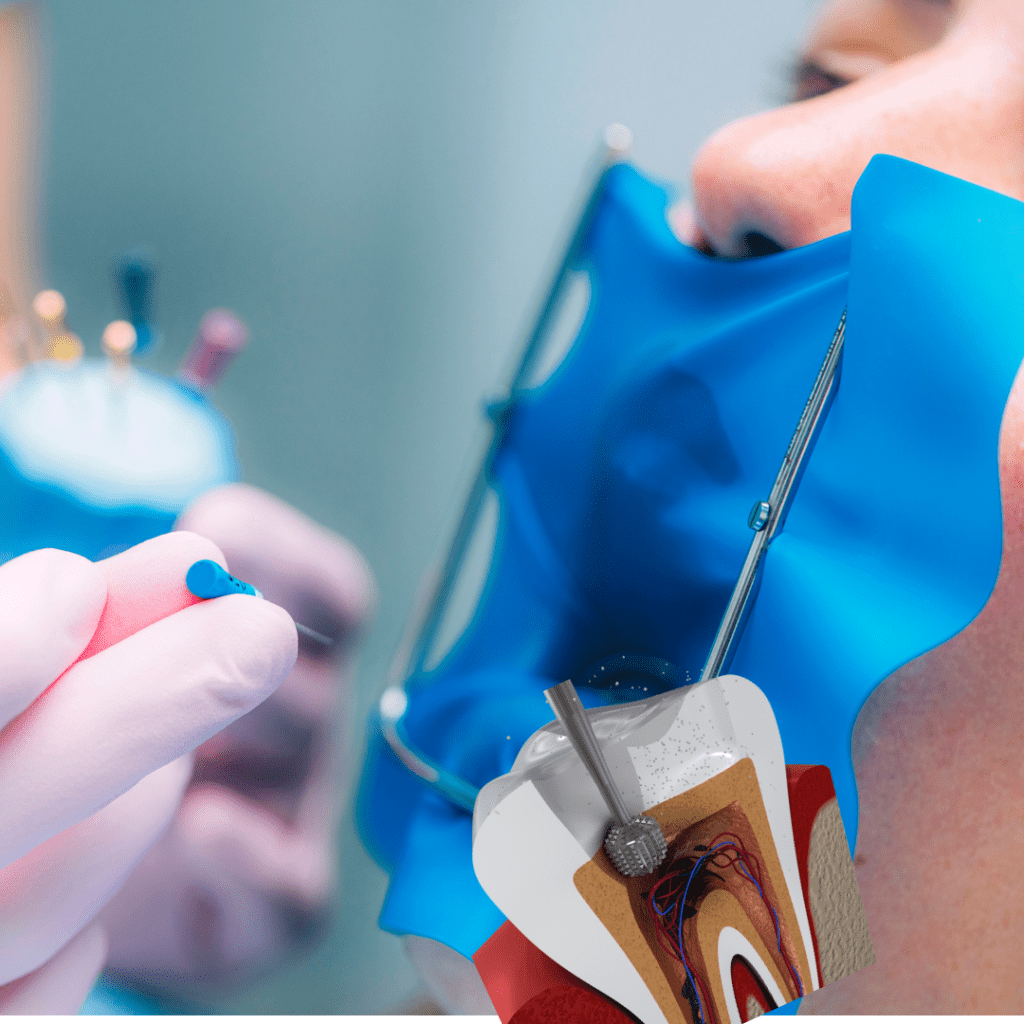

ENDODONCIA

- tratamiento de conducto de uniradiculares

- Tratamiento de conducto de birradiculares

- Tratamiento de conducto de multiradiculares

- Remoción de pernos.

- Cirugías Apicales